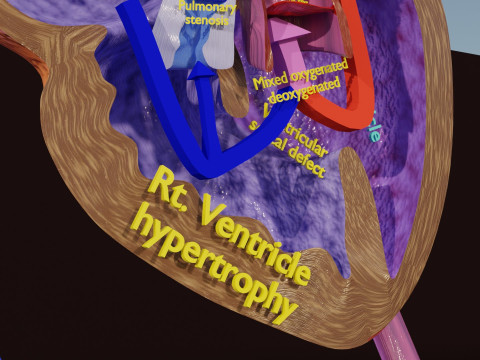

The model meshes include adult circulation versus circulation in Tetralogy of Fallot (TAF), arrow labels and text labels. The blood flow in a patient with Tetralogy of Fallot is outlined in this model. To contrast it to normal blood circulation a separate model of normal circulation is included. The Tetralogy of Fallot (OVER RIDING OF AORTA, PUL STENOSIS, VENTRICULAR SEPTAL DEFECT, RIGHT VENTRICULAR HYPERTROPHY), fossa, ligament teres , venosus, and arteriosus are duly depicted with proper labelling and blood flow directional arrows. Excellent model for teaching, demonstration and knowlegde of human body. The models include both procedural and image textures blend files separately. The texture file include diffuse, roughness and normal png and jpeg based on non overlapping UV maps.